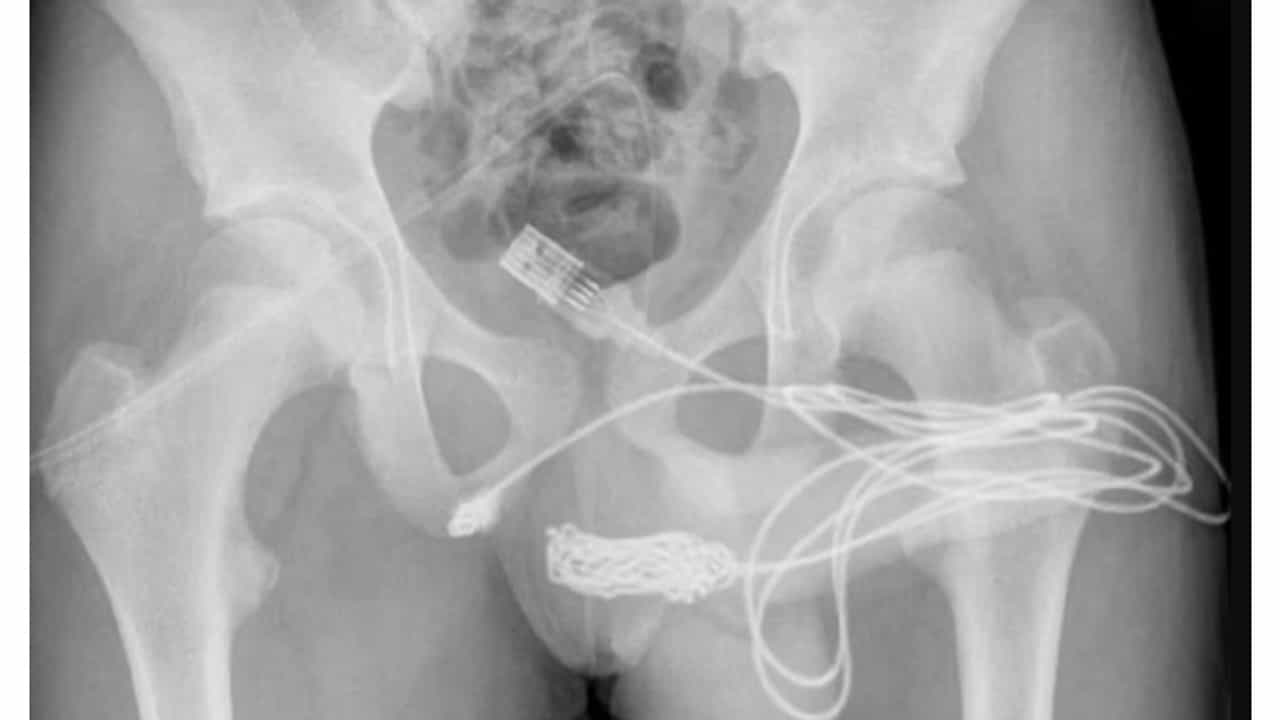

एक्स-रे अहवालात डॉक्टरांना यूएसबी केबलचा आकार आणि स्थिती समजली. यानंतर मुलाला तातडीने शस्त्रक्रियेसाठी हलवण्यात आले. आधी डॉक्टरांनी मोठ्या प्रयत्नांनंतर केबलची गाठ बाहेर काढली. यानंतर उर्वरित USB बाहेर काढण्यात यश आले.